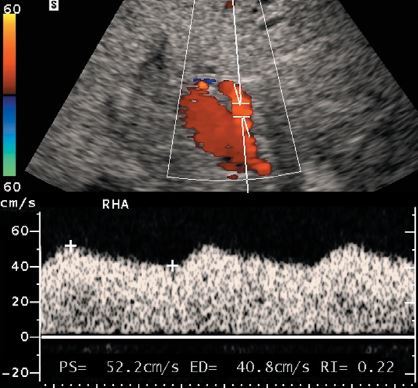

HA thrombosis following liver transplant

• Significant hepatic artery stenosis and hepatic artery thrombosis with collateral flow can be detected with Doppler scanning by noting a blunted arterial waveform distal to the stenosis. Blunting can be quantified in several ways.

• The easiest is by measuring the resistive index. If the resistive index is less than 0.4, the waveform should be considered severely blunted, and a diagnosis of hepatic artery stenosis or thrombosis should be made.

• In this case, the left hepatic artery serves as a collateral receiving blood from the left gastric artery

• Since the bile ducts are dependent on hepatic arterial supply, arterial thrombosis causes biliary ischemia and can produce strictures or complete necrosis of the ducts.